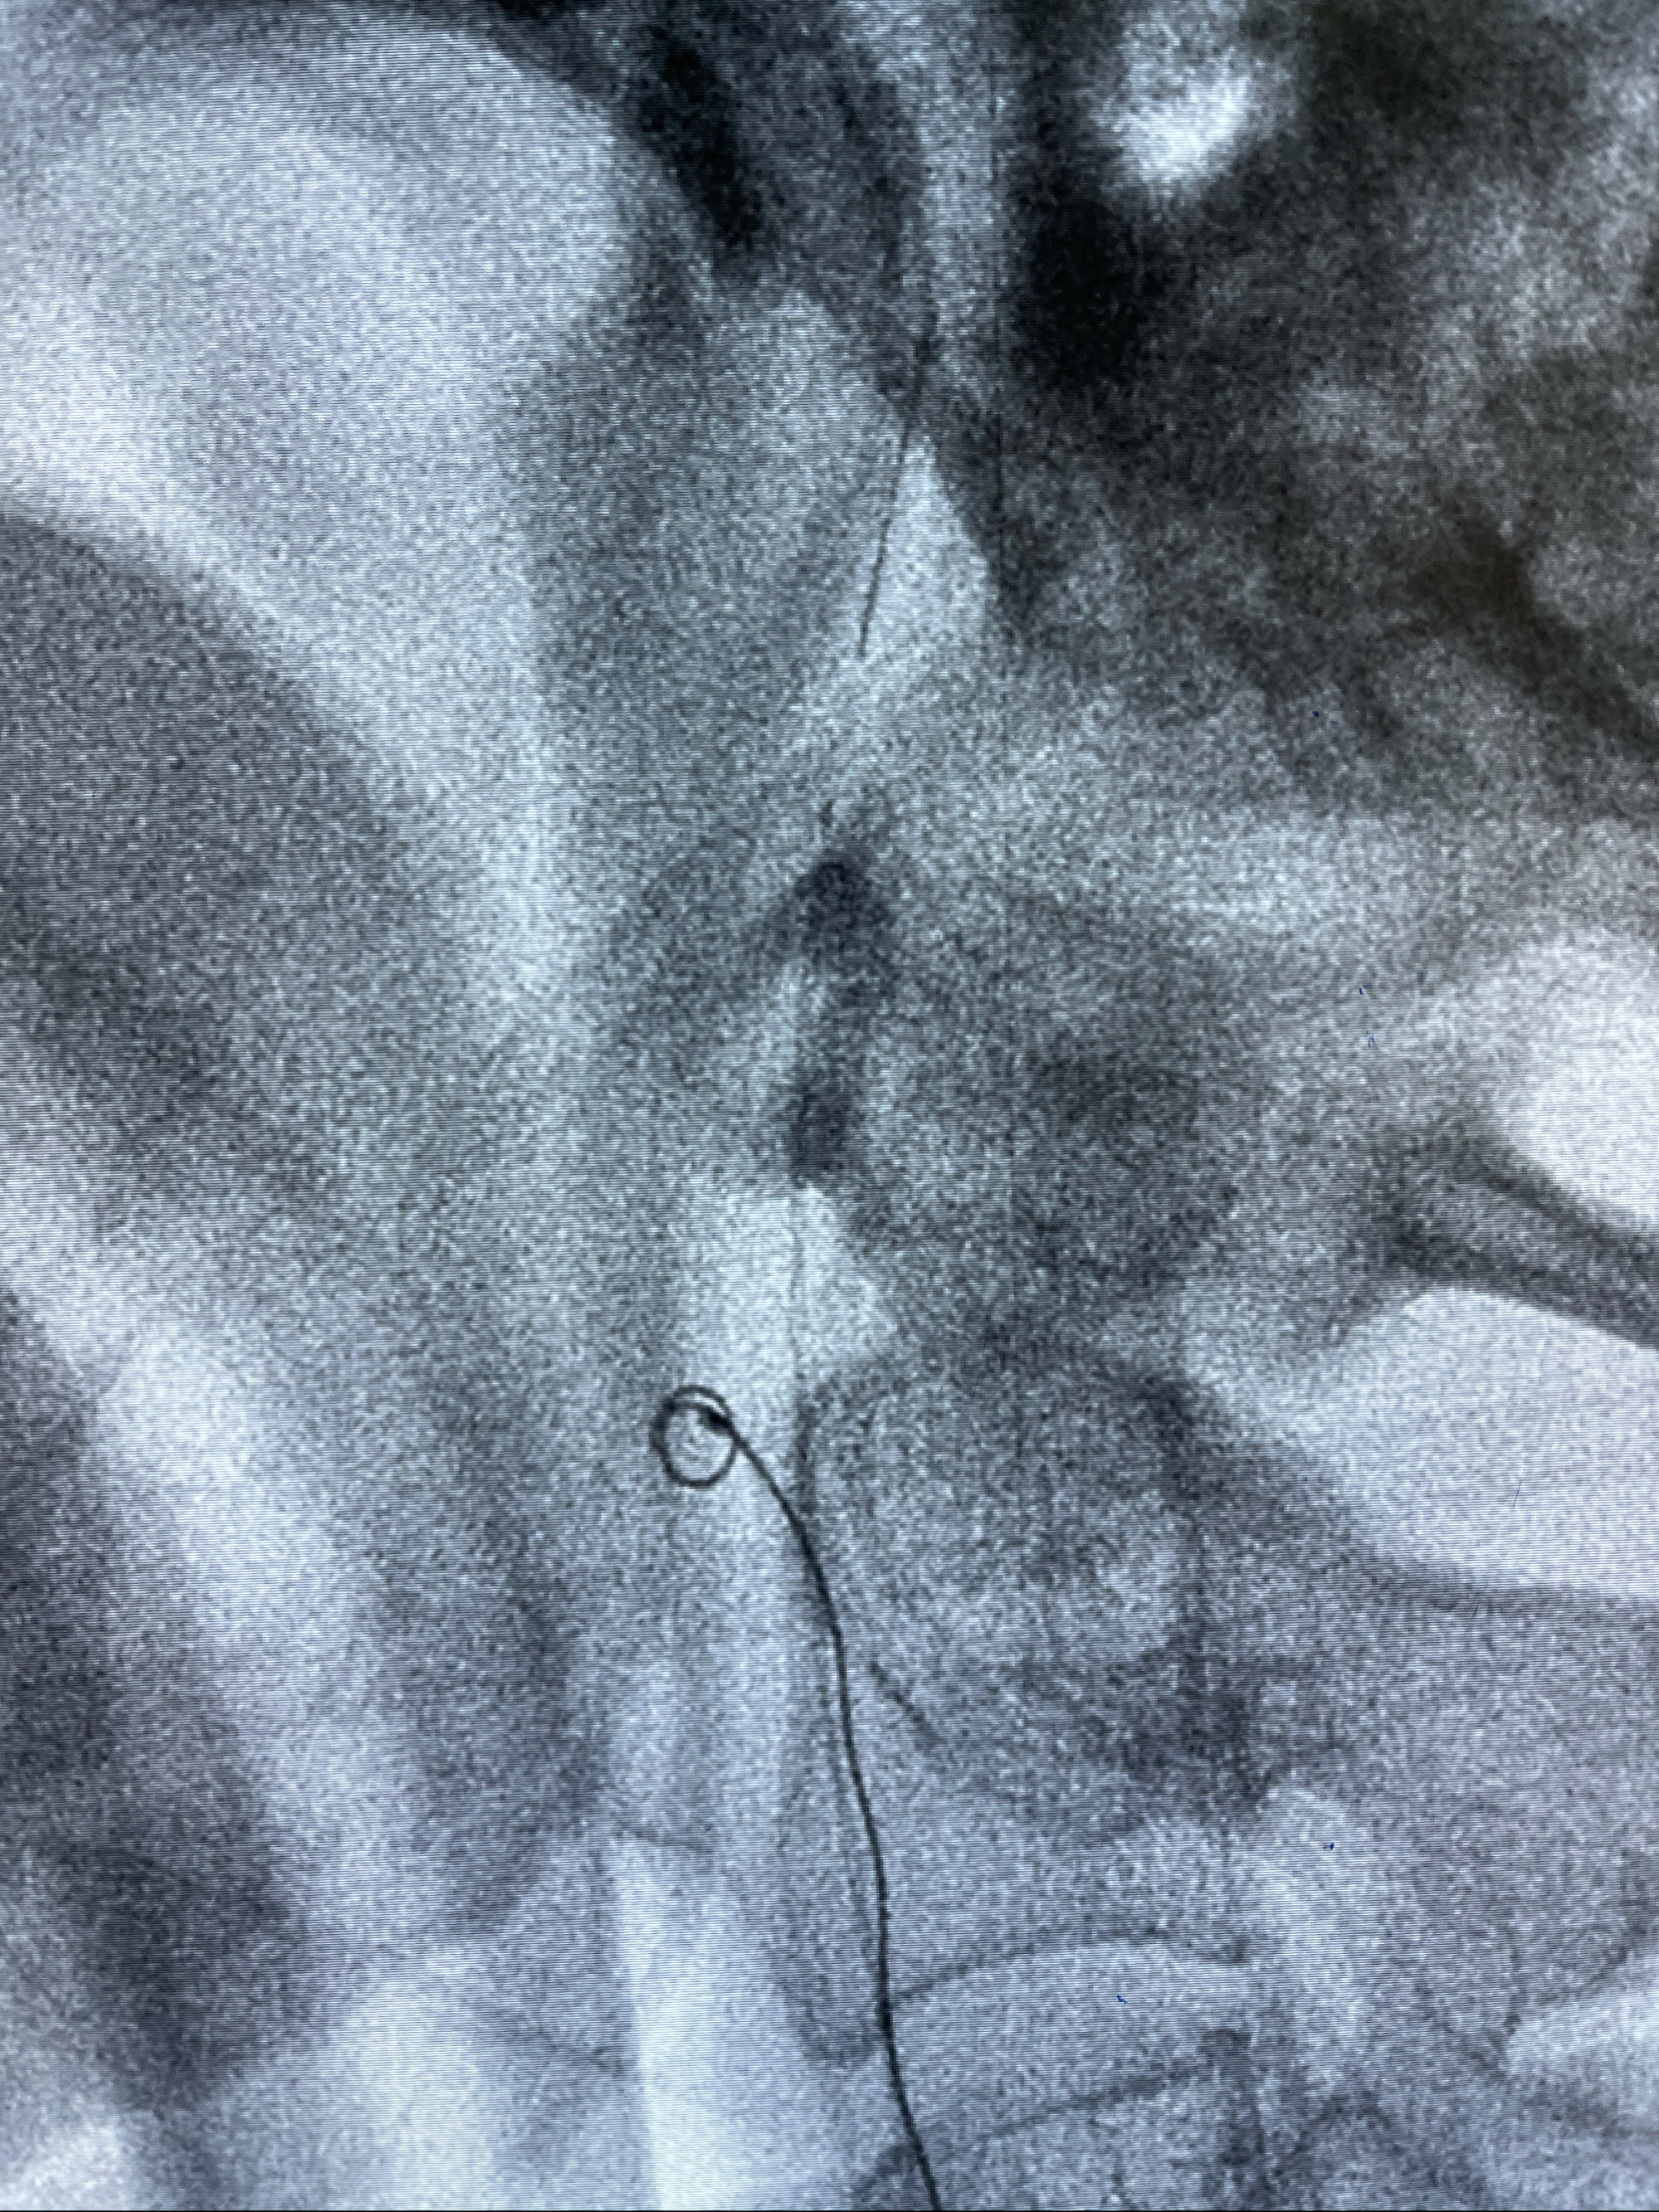

Echelon10 45°角微导管塑形后到位

8mm-40cm微弹簧圈成篮

支架释放,透视下